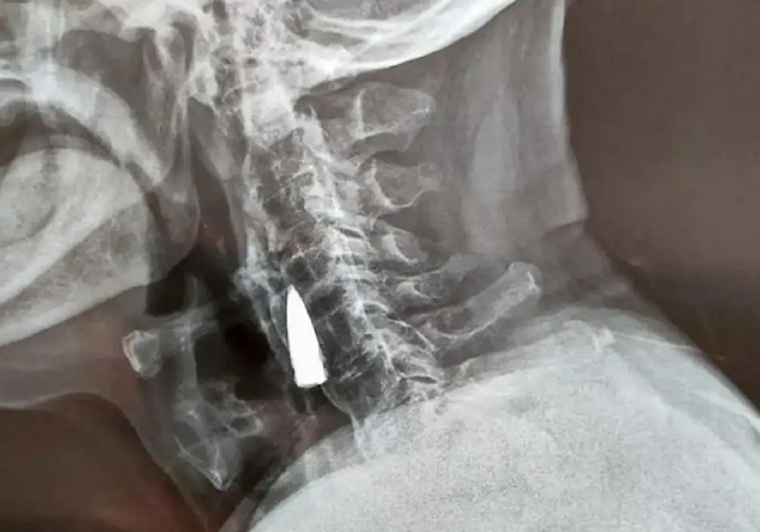

El descubrimiento del proyectil en el cuello de Zhao He se dio el 21 de octubre pasado durante un examen médico en el hospital de Linyi, provincia de Shandong. Allí le realizaron estudios físicos y comprobaron, por una radiografía, la existencia de tal munición.

Luego de su vida militar, que duró más de 20 en combate, se dedicó a trabajar en fábricas. Lo extraño es que nunca se percató de que podía tener algo incrustado en su cuello. Por lo que dijo el hombre, podría estar alojada allí desde 1944, el año previo a las rendiciones del Eje y el fin de la Segunda Guerra Mundial.